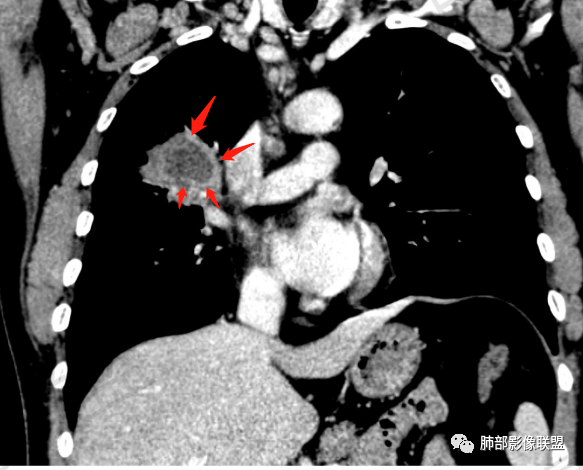

多发树芽,病灶边缘模糊的GGO

环形强化

坏死区几乎是寸草不生

纵隔淋巴结肿大并不明显,就这一个肿大较明显,但仍呈椭圆形,中心少许坏死。

怎么看怎么不符合恶性,远端并不是明显的阻塞性炎改变,一是主要表现为树芽和结节,二是未按责任支气管分布。

1、坏死区内寸草不生;2、病灶环形强化;3、远端树芽和结节;4、远端不是阻塞性炎症,而是树芽和结节,右肺上叶前后段都有,后段为主,而堵塞的支气管应该是前段;这些树芽的位置不是堵塞支气管的责任区;5、支气管不是突然截断堵塞,而是逐渐狭窄;6、纵隔淋巴结是椭圆形增大,内有坏死,不是肿瘤的圆形饱满;7、支气管周围粘液样坏死,符合仙人掌结核改变;